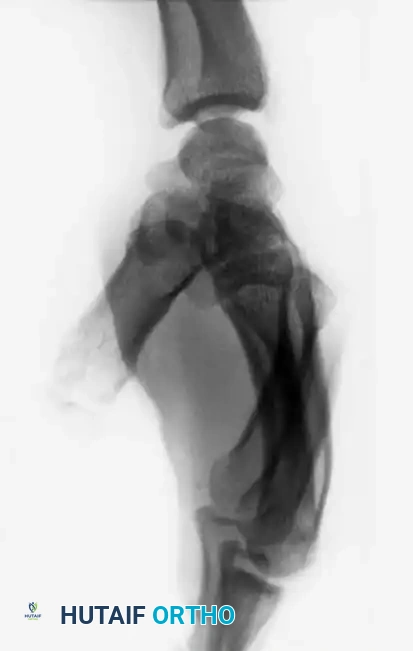

Fig. 64-31 Dislocation of fourth and fi fth carpometacarpal joints. A, Clinical appearance of hand before reduction. Note dorsoulnar hand swelling consistent with injury. B, Posteroanterior view. C, Lateral view. D, Oblique view. E and F, Traction was adequate to reduce, and splint was satisfactory to maintain reductions.